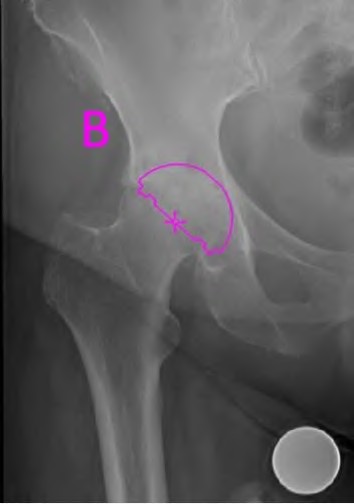

An 82-year-old woman falls and sustains the fracture shown in figure A. She denies any history of dislocation or prodromal pain prior to her fall. What is the most appropriate treatment?

The radiograph demonstrates a periprosthetic femur fracture extending to the tip of the stem. The long spiral fracture is consistent with a loose implant. The bone stock is sufficient. Therefore, this fracture pattern would classify as a B2 using the Vancouver classification system. The Vancouver classification for periprosthetic femoral fractures is simple yet incorporates all the pertinent factors such a location, stem fixation, and bone stock. Type A is a trochanteric fracture- lesser or greater. These can be treated non-operatively usually and ORIF if symptomatic. Type B fractures are around or just below the stem and are subdivided into three types. Type B1 is a fracture with a well fixed stem.

The treatment is cable plating or allograft struts or a combination of the two. Type B2 is a fracture with a loose stem with good bone stock. The treatment is a cementless porous coated long stem atleast two diameter length past the

fracture site. Type B3 is a fracture with a loose stem and comminution. For younger patients, use cementless porous coated long stems with allograft struts. For older patients, consider a tumor prosthesis. Cement fixation is sometimes necessary Type C is a fracture well below the stem tip. These can be treated independently of the prosthesis.

Springer et al showed optimal outcomes with revision involving long extensively-coated femoral stems for Vancouver B fractures.

Masri et al review the classification and treatment of periprosthetic femur fractures.